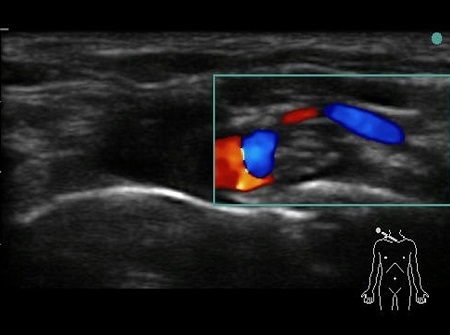

- The first structure to locate is the round pulsating hypoechoic subclavian artery (A), lying on top of the hyperechoic first rib (R). Use Doppler to assess for vessels. See Fig. 2.

Fig. 2. Bidirectional Doppler used here to highlight the subclavian artery.

- The subclavian vein (V) is found more medially to the artery. The anterior scalene muscle inserts onto the first rib between these two vessels (A and V), but occasionally there are anatomical variations (4) where both vessels are together between the insertions of both the scalene muscles (anterior and middle ones).

Hypoechoic vessels may be seen among the brachial plexus nerves (also round hypoechoic structures). Because they have similar appearance, it is important to differentiate them (colour Doppler MUST be used) (16). See Fig. 9.

Fig. 9. Doppler highlighting subclavian artery with dorsal scapular artery passing posteriorly through brachial plexus.